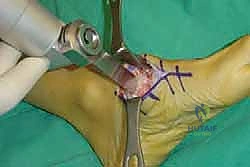

6. التثبيت الصلب (Rigid Fixation)

لضمان التحام العظام لتصبح عظمة واحدة صلبة، يجب تثبيتها بقوة هائلة حتى لا تتحرك أثناء فترة الشفاء. يتم استخدام مسامير معدنية متطورة (Screws)، أو شرائح معدنية خاصة (Plates)، أو دبابيس طبية متخصصة (Staples) مصنوعة من التيتانيوم الآمن على الجسم.

7. الإغلاق والضماد

بعد التأكد التام من وضع العظام وثباتها باستخدام جهاز الأشعة السينية داخل غرفة العمليات (C-Arm)، يتم إغلاق الشقوق الج